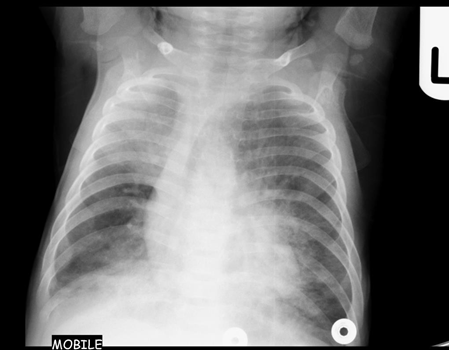

Chest x-ray is not usually diagnostic but may show bilateral diffuse parenchymal infiltrates with a “ground-glass” or reticulogranular appearance, but can be normal or have only mild parenchymal infiltrates. The earliest infiltrates are perihilar, progressing peripherally before reaching the apical portions of the lung.